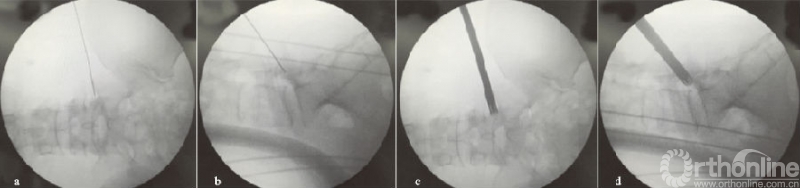

向上游离的腰椎间盘突出症由于没有上关节突的阻挡,一般通过水平穿刺或向上稍倾斜角度的穿刺,不需要行关节突成形,利用工作套管的活动度及带角度的髓核钳,可相对容易摘除椎间盘(见图4a-d);而对于向下游离的腰椎间盘突出症,要根据游离物的大小及方向,来行适当的关节突成形以扩大偏下方的椎间孔区,以顺利摘除椎间盘,减少残留可能(见图4e-h)。

(a)(b)L4/5节段向上游离型突出穿刺置管透视图,其中(a-b)为一级导杆定位图;(c)(d)工作通道放置图;(e-h)L4/5节段向下游离型突出穿刺置管透视图,其中(e-f)为保护套管下环锯行FP图;(g)(h)工作通道放置图

图4 L4/5节段游离型突出穿刺置管图